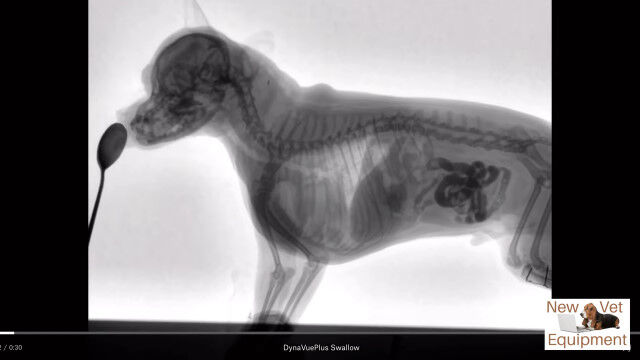

動物用レントゲンシステム、ダイナビューを用いて撮影された、犬がエサを食べる最中の体内の様子。

口から食道を通り、ゆっくり胃袋へ流れ込む様子が動画ではっきり確認できる。

Youtubeの概要欄に記載がなくて分からなかったけど、これ犬種はなんだろうね。

Veterinary Fluoroscopy - Watch the Swallow!